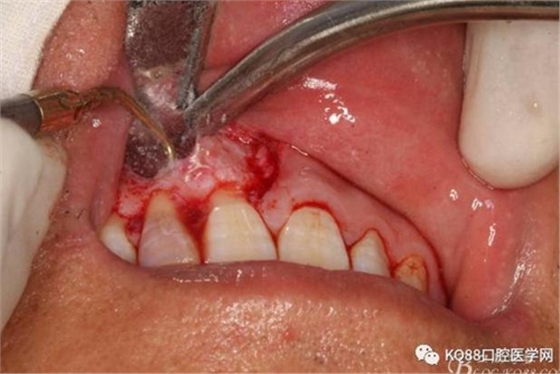

圖14.超聲骨刀切除根尖組織3mm。

圖15.超聲骨刀修整切除后的根面,使其12根斷面平整光滑。